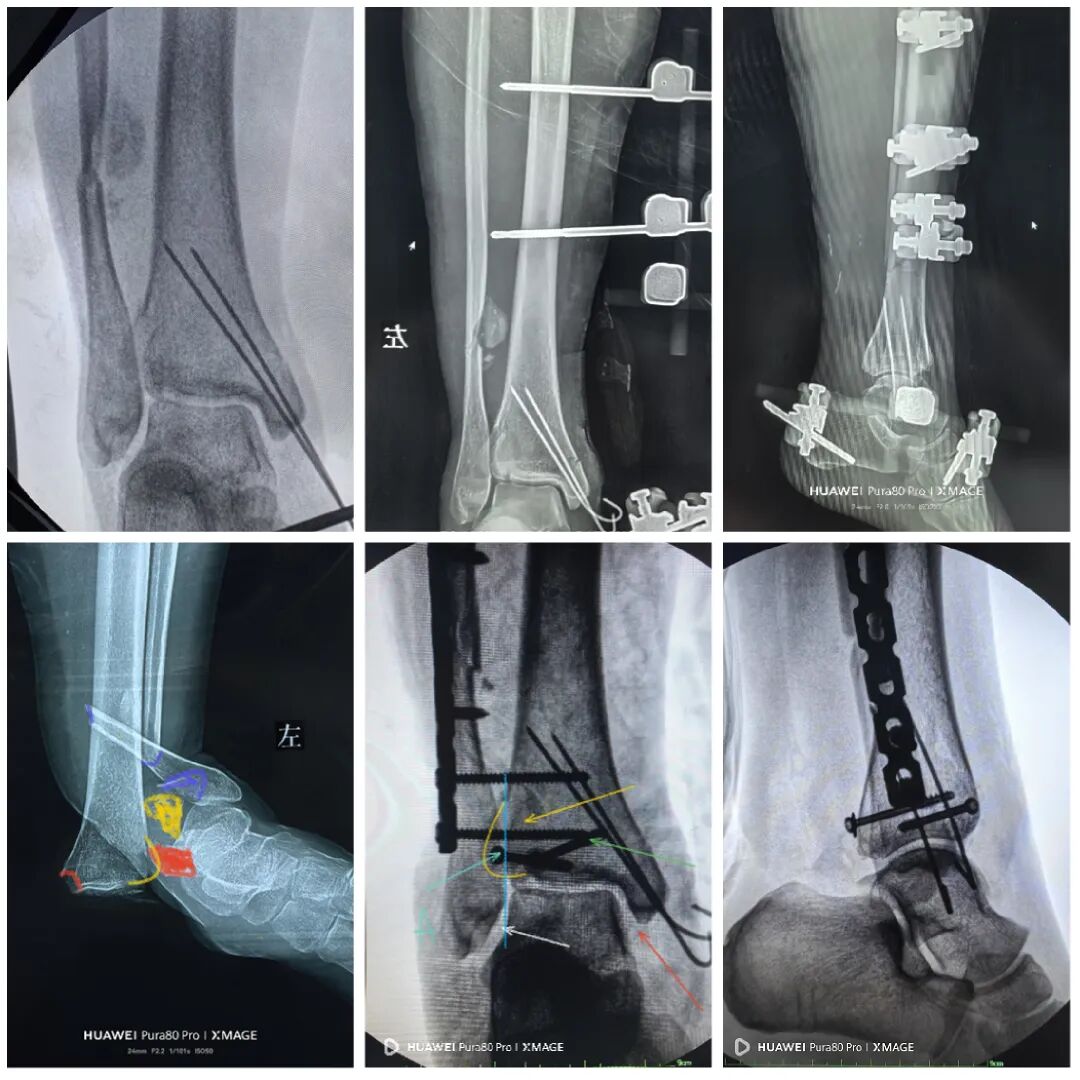

术后1周

内侧伤口愈合良好

行二次确定性手术

换钉子,调整下方向

解剖复位

最后做下胫腓

两个位置螺钉固定

下胫腓关节复位

内踝间隙恢复

缝合前侧和后外侧切口

取外架

缝合钉道